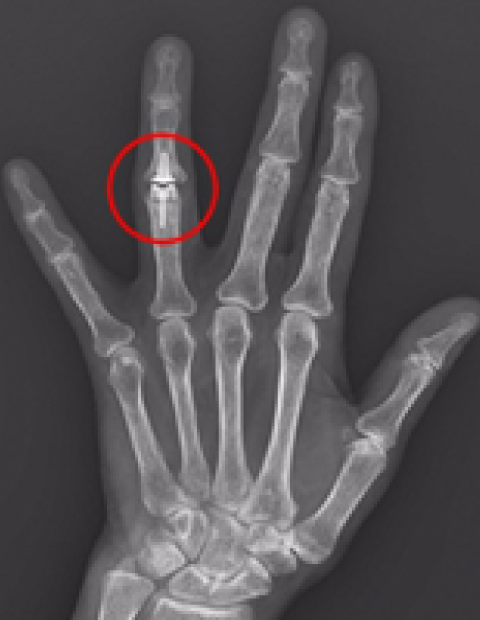

손가락 인공관절 수술

2016.04.01

2016.09.09